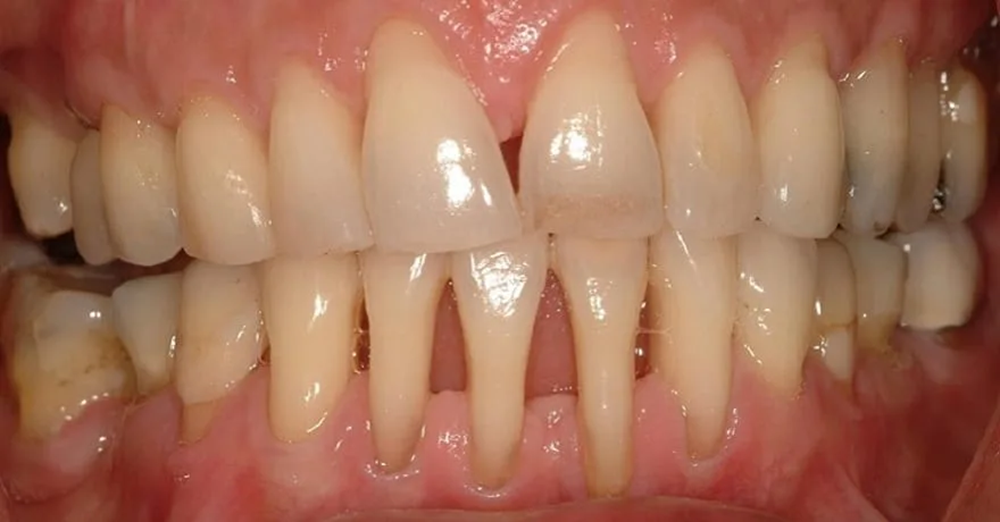

Viêm nha chu là tình trạng viêm nhiễm nghiêm trọng lan sâu xuống dây chằng và xương ổ răng. Đây là nguyên nhân hàng đầu gây tiêu xương ngay cả khi không niềng răng. Nếu vẫn cố chấp dịch chuyển răng trên nền nha chu yếu, lực chỉnh nha sẽ đóng vai trò như một tác nhân cộng hưởng, thúc đẩy quá trình tiêu xương diễn ra nhanh hơn (tiêu xương bệnh lý), làm trầm trọng thêm tình trạng mất bám dính và khiến răng lung lay nhanh chóng.

Răng bị tiêu xương, tụt lợi ngay cả khi không niềng răng

Khách hàng cần phải điều trị triệt để viêm nha chu trước khi gắn mắc cài. Bác sĩ chỉnh nha cần phối hợp chặt chẽ với bác sĩ nội nha để đảm bảo hiệu quả điều trị. Chỉ khi các túi nha chu đã được xử lý, tình trạng tiêu xương được kiểm soát và mô mềm đã ổn định hoàn toàn thì mới có thể niềng răng. Trong suốt quá trình chỉnh nha cho người có tiền sử nha chu, bác sĩ phải sử dụng lực nhẹ, thăm khám định kỳ hàng tháng và kiểm tra phim X-quang thường xuyên để đảm bảo răng vẫn nằm trong giới hạn an toàn của bản xương.